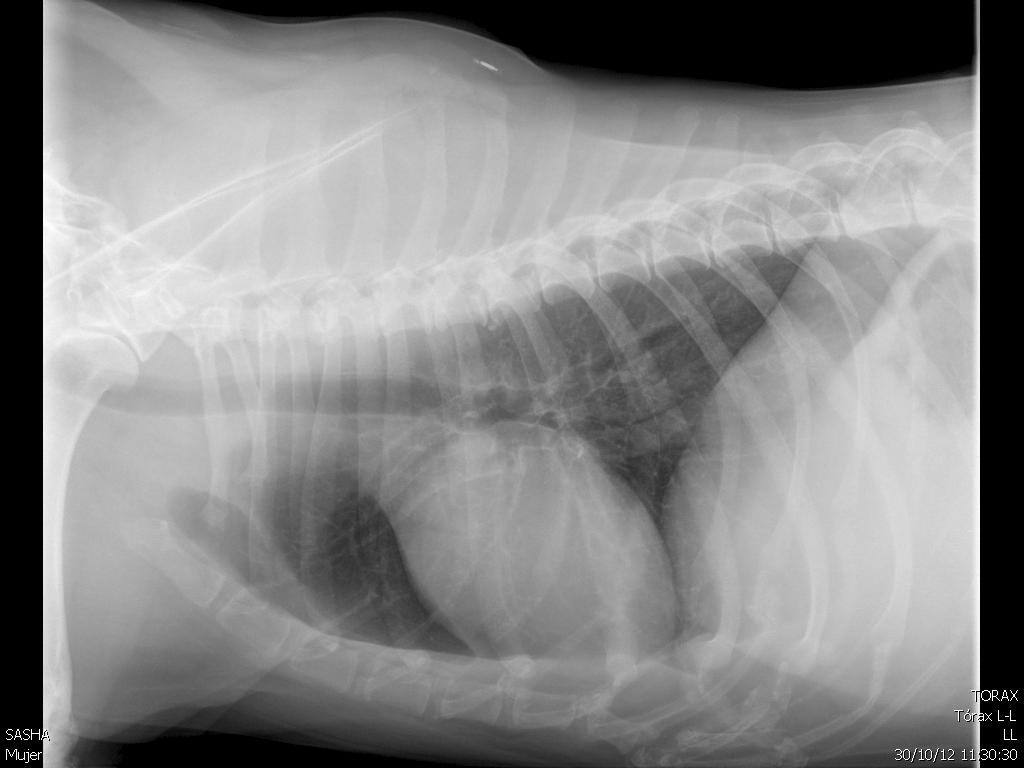

Rx

torácicos sin alteraciones.